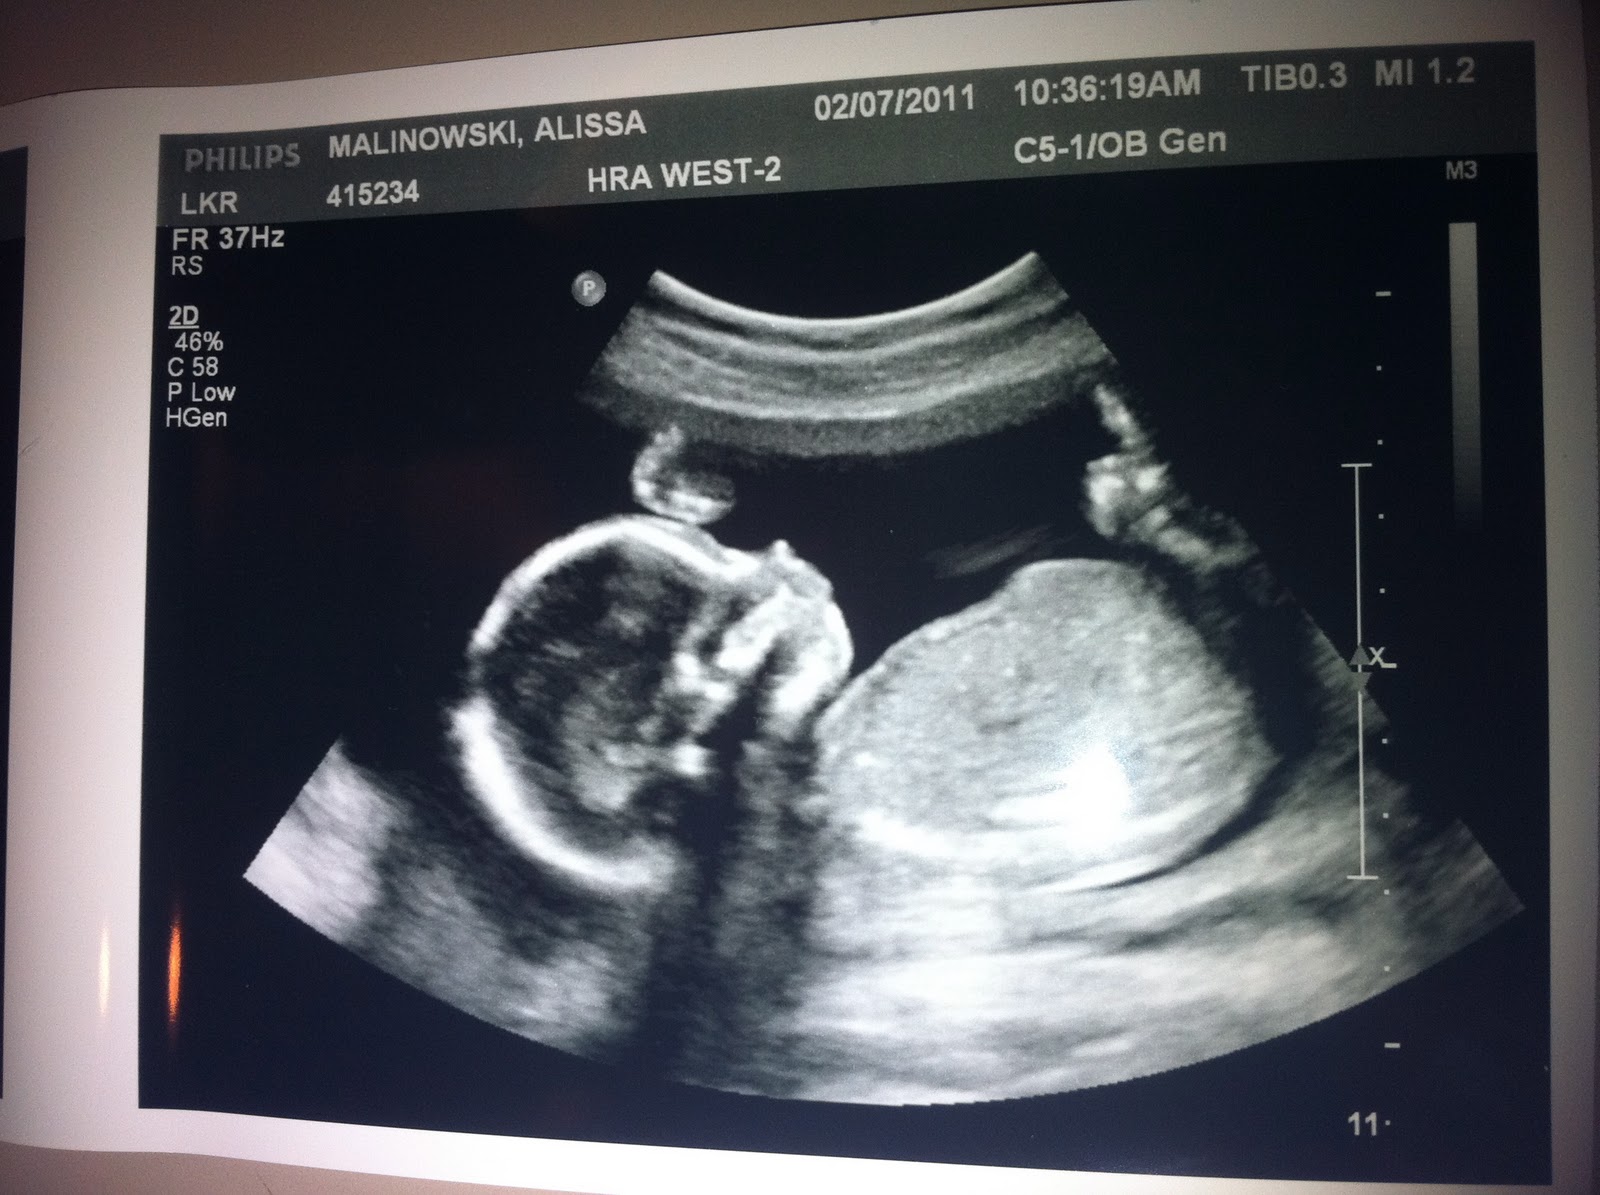

First photo of Baby Mal

I can not express how filled with JOY we are today after our ultrasound! It was incredible. And here now to announce that Baby Mal is a BOY!! A healthy 9 oz at 18 weeks and 6 days, and super cute already :) We were in awe watching him stretch, kick and squirm on the screen - it was absolutely amazing! Here's one of the ultrasound pictures we got to take home....our first photo of the little guy.